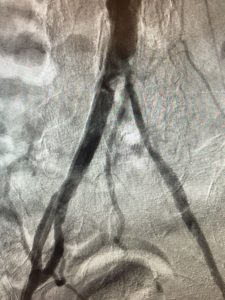

Konvansiyonel anjiografi ile de işlem sırasında hem tanı konabilir hem de tedavi gerektirir durumlarda balon, stent veya diğer işlemlerin yapılması mümkündür.

Girişimsel tedavi yöntemleri anjiografi eşliğinde yapılan müdahalelerdir. Dünyada ve ülkemizde sık olarak uygulanan etkili bir tedavi yöntemidir.

İşlem esnasında daralmış veya tıkanmış damar bölgesi ince tel sistemleri ile geçilip darlığın yerleşim yeri ve uzunluğuna bağlı olarak aynı tel sistemi üzerinden bölgeye ulaştırılan aterektomi (damar tıkanıklığına sebep olan plakların temizlenmesi), balon ve stent sistemleri ile tedavi mümkün olmaktadır. Hastalar işlem süresinde kullanılan tekniklere ve işlemin süresine göre işlemden 6-8 saat sonra veya ertesi gün taburcu edilmektedirler.